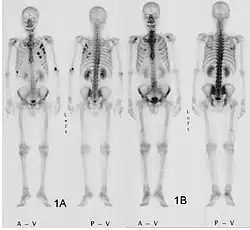

Тревожные симптомы, к которым относится прежде всего появление крови в кале, — основание для колоноскопии, то есть визуального исследования внутренности толстой кишки с помощью эндоскопа. Его трубка снабжена осветительным устройством и миниатюрной камерой, передающей изображение на большой цветной монитор. Применение эндоскопа позволяет осмотреть всю внутреннюю поверхность толстой кишки. В случае выявления мелких полипов их можно удалить, избежав злокачественного развития.